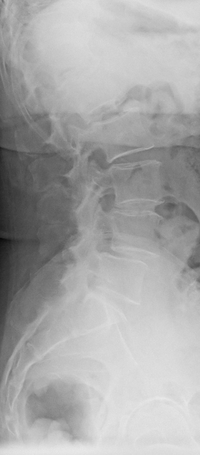

Wegweisend ist neben der klinischen Untersuchung die konventionelle Röntgenaufnahme der Lendenwirbelsäule in zwei Ebenen. Hier erkennt man einen Versatz zwischen den Wirbelkörpern. Eingeteilt wird die Spondylolisthesis in Grade nach Meyerding.

• Meyerding I°: Versatz der Wirbelkörper zueinander um weniger als 25 % der Wirbelkörpertiefe,

• Meyerding II°: Versatz um 25–50 %,

• Meyerding III°: Versatz um 50–75 %,

• Meyerding IV°: Versatz um mehr als 75 %.

• Spondyloptose: vollständig von vorne abgerutschter Wirbel